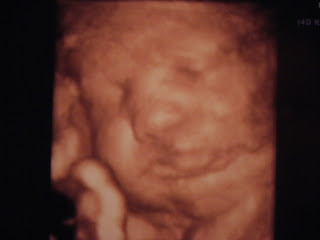

Dados da eco 4D de ontem

Então cá vamos:

Peso: 2718g

Tamanho: 30cm da cabeça ao rabo + pernas (Ai!)

Cabelo: muito (1cm de cabelo) Note to myself (marcar cabeleireiro)

Lábios: grossos como os da mãe

Bochechas: grandes como as da mãe

Comportamento: continua a fazer birra, resumindo não gosta das ecos

Melhor amigo: o cordão umbilical, afinal é dali que vem a comida, por isso há que não o perder de vista e mantê-lo por perto, tipoooo... abraçadinho e junto à cara. Ah e dar beijinhos nele, já agora.

Coxa: grossa! 2cm de muque e 6mm de gordura (ainda bem que temos uma bicla de manutenção)

Posição: já virou, de cabeça para baixo, mais do lado direito. Afinal o que espeta nos rins é o cu mesmo!

Fisionomia: é a cara da mãe.

Data provável de nascimento: entre 19 de Janeiro e 29 de Janeiro.

Por dentro:

Não há tempo nem palavras para mais! Espero que tenham mãos fortes para apertar estas bochechas! Ah e olhem bem a personalidade da nossa filhota: língua de fora!